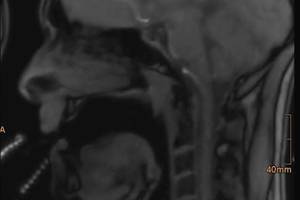

Das Freiburger Institut für Musikermedizin zeigt mit Filmen, was beim Blasinstrumentenspiel im Körperinneren passiert Freiburg, 10. Aufnahme eines Musikers im Kernspintomografen, der auf einem Plastikinstrument aus Schläuchen spielt. Quelle: Helbling Verlag GmbH Wenn Bläserinnen und Bläser auf ihrem Instrument spielen, laufen die entscheidenden Vorgänge im Körperinneren ab: in Mundhöhle und Rachen, in Kehlkopf und Brustraum.